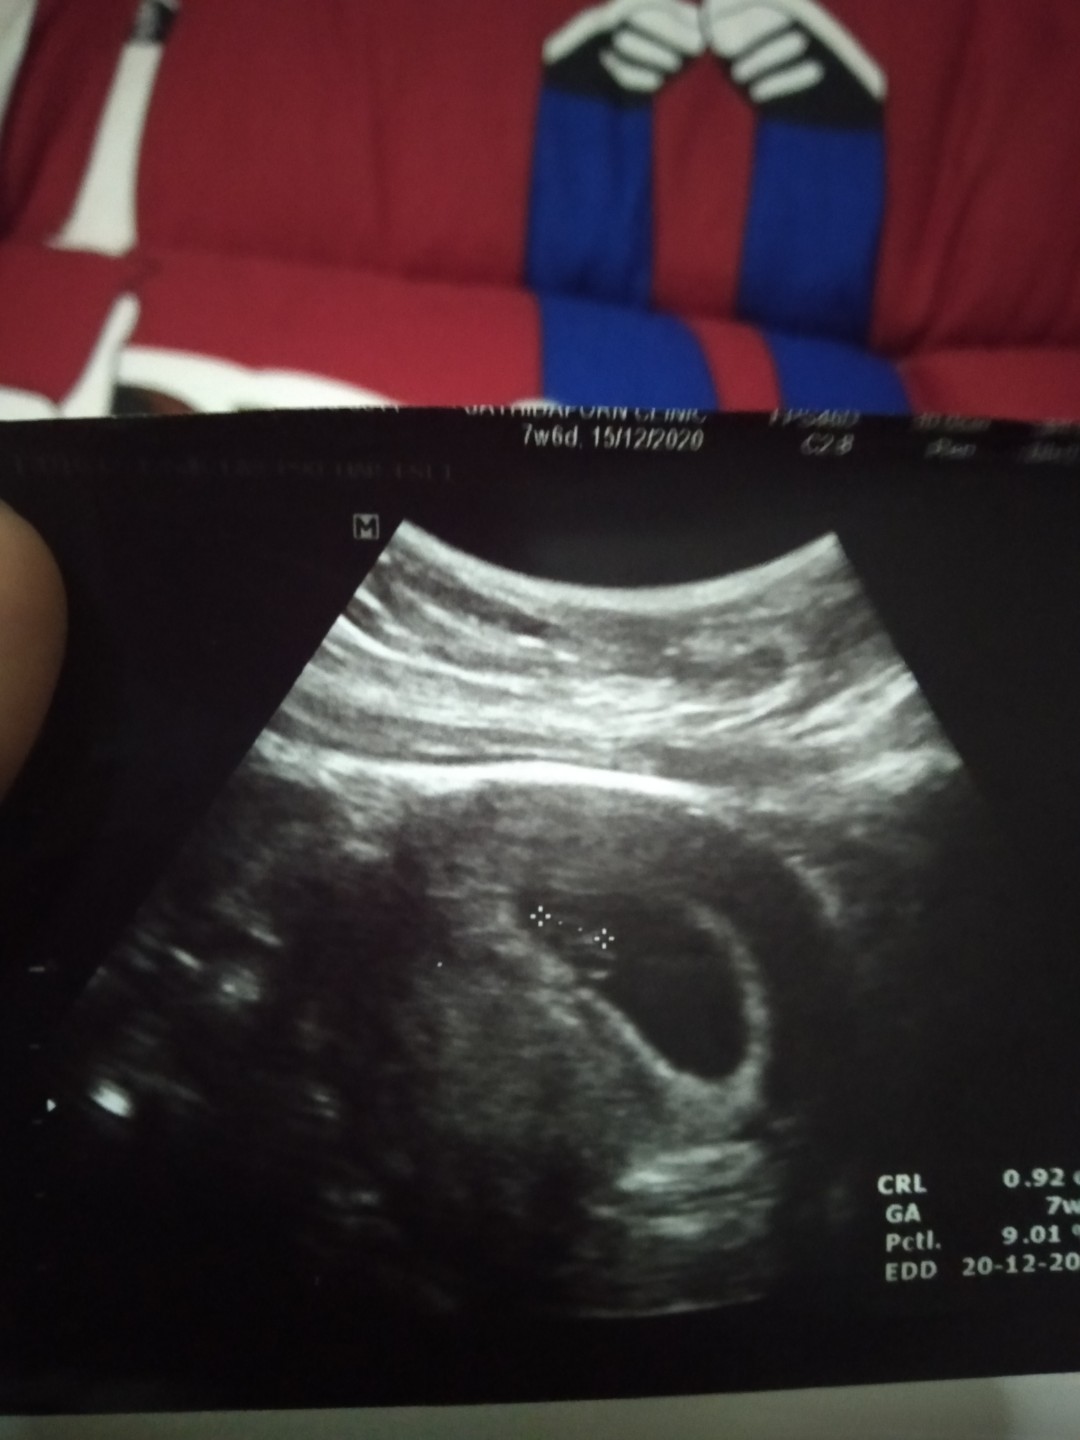

18ธันวาจ้า

16 ธ.ค 63 ค่ะ